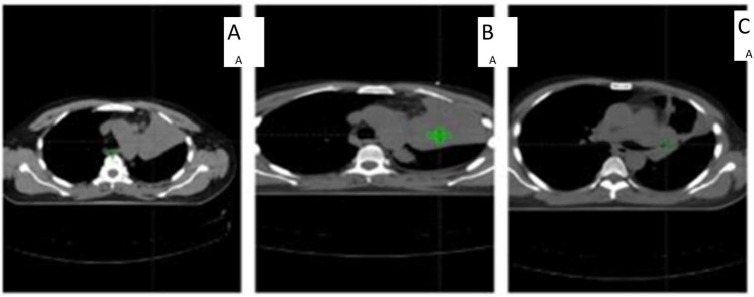

Methods: This prospective study was conducted at Kasr El-Aini Center of Clinical Oncology and Nuclear Medicine, Cairo, Egypt from January 2019 to December 2020. Thirty patients with pathologically proven, limited-stage small cell or stage I-II non-small cell lung cancer who were either not fit for or refused surgery or had stage III disease were recruited and underwent treatment planning to receive 60 Gy on a conventional 3D conformal radiation schedule with platinum-based chemotherapy. All patients underwent computed tomography (CT) planning within 2 and 4 weeks of starting radiation therapy to assess the need for adaptation. Pulmonary function test and echocardiography findings were assessed at the end of treatment and at 3 and 6 months after treatment, and were compared to the baseline.

Results: We found a significant reduction in mean value of the planning target volume (PTV) in the CT scans at the second (331 cm3) and fourth (257 cm3) weeks of treatment as compared to baseline (342 cm3) (p-value < 0.0001). Adaptation decreased the dose to the organ at risk with statistical significance and with improvement of the target coverage. At week 2 of radiotherapy, the need for adaptation was correlated to the conformity index (p = 0.0473), esophageal V35 (p = 0.0488), esophageal V50 (p = 0.0295), and its mean dose (p = 0.0087). At week 4 it was correlated to forced expiratory volume in 1 second (FEV1) (p = 0.0303), ratio between the forced expiratory volume in 1 second and the forced vital capacity (FEV1/FVC) (p = 0.0024), and echocardiography (p = 0.0183).